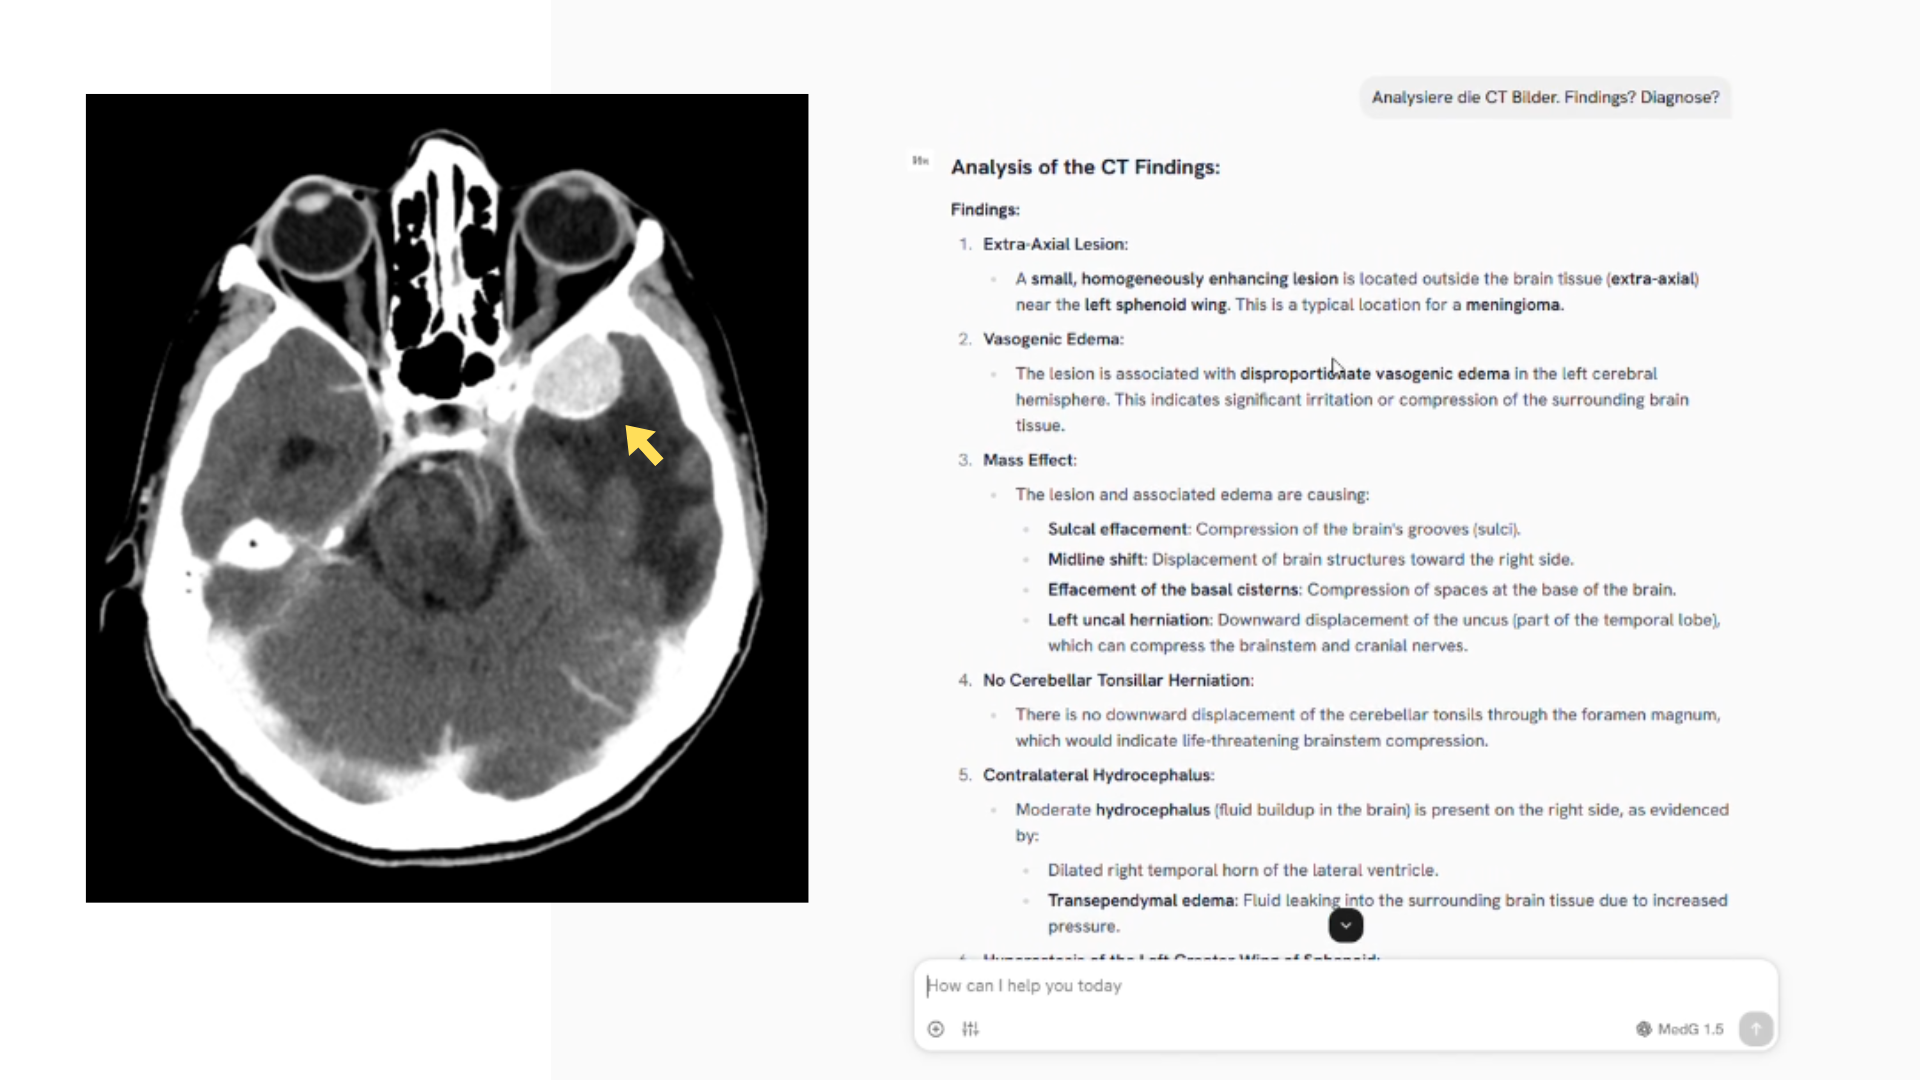

Sichere klinische Kommunikation, Dokumentenarbeit und Wissenszugriff, ohne Datenchaos. Vicy (MedGPT.chat) verbindet Chat & Suche mit verifizierten Quellen aus KIS/EPA, Dokumenten, SOPs und M365. Mit Rollenrechten, Audit-Log und klarer Eskalation bei Unsicherheit.

Praxisbeispiele

Ergebnisse aus der Praxis

Schichtwechsel unter Zeitdruck. Kritische Infos stehen im Verlauf, im Befund-PDF oder in Mails und gehen im Alltag unter.

Teams fragen im Chat patientenbezogen nach, Vicy beantwortet mit Quellenzitaten (Dokument, Abschnitt, Datum). Fehlt Datenlage, eskaliert Vicy ('Ich weiß es nicht') statt zu raten.